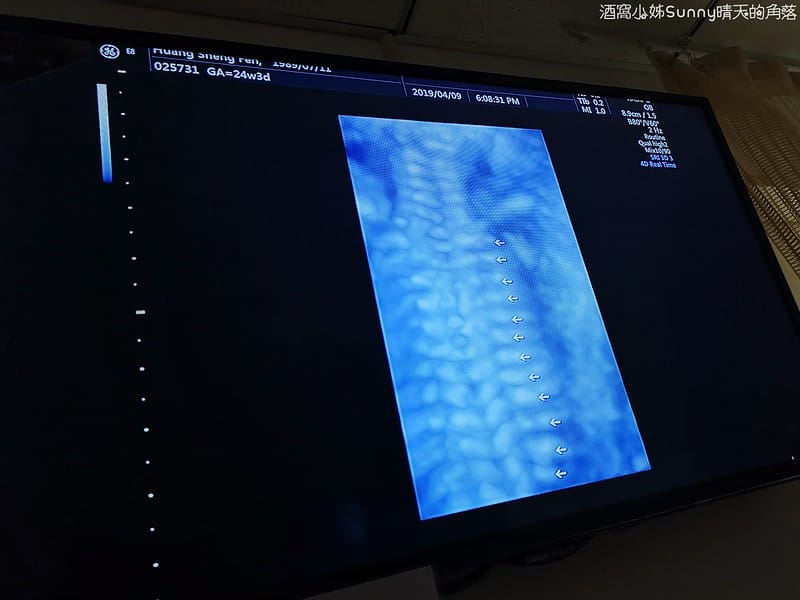

11. 彩色都卜勒超音波檢查臍動脈及子宮動脈血流

▼這個應該比較好懂!醫生在數寶寶的肋骨一共有12根❤